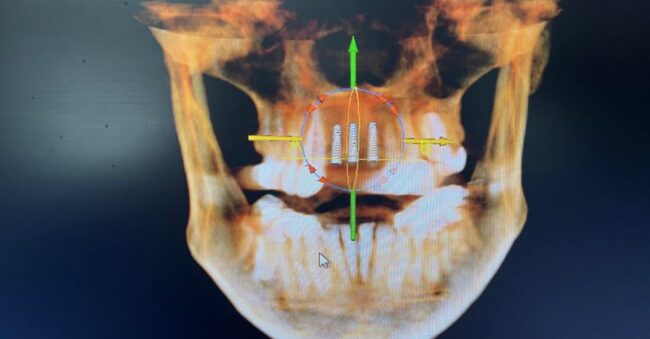

Dental Implants for Missing Teeth: Permanent, Natural-Looking Solutions Dental implants are the gold standard for replacing missing teeth, restoring both function and aesthetics with long-lasting results. As advanced tooth replacement solutions, dental implants provide exceptional stability for crowns, bridges, and implant-supported dentures—helping you regain a confident, natural-looking smile. Dental implants are small, biocompatible titanium posts…